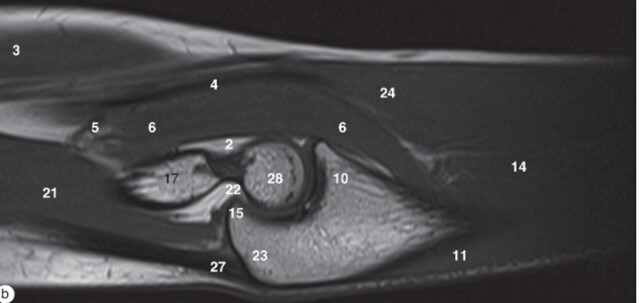

11

Q

Label 3,6,8,8,16,17,19,25

A

3=Biceps brachii muscle

6=Brachialis muscle

8=Capitulum of humerus

9=Cephalic vein

16=Radial head

17=Humerus

19=Triceps brachii

25=Radius

12

Label 3,6,9,17,21,23,28

6-Brachialis muscle

9=Coronoid process

21=Triceps brachii

23=Olecranon process of ulna

28-Trochlea of humerus